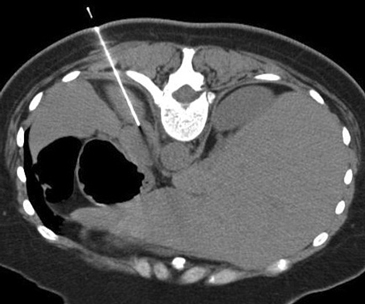

e) Biopsia percutánea guiada por TAC

En la actualidad su uso es excepcional y su indicación esta reservada para casos en que las técnicas no invasivas no son diagnosticas y en casos en que se sospecha un linfoma y es necesario tipificarlo. En el lado derecho si la masa es pequeña se prefiere el abordaje transhepático (Figura 16 a) y en el lado izquierdo la vía dorsal posterior (Figura 16 b).

La vía transhepática sólo se realiza con aguja fina, de manera que si en el lado derecho es necesario obtener mayor cantidad de tejido, la biopsia se realiza con una aguja de tipo trucut pero el acceso tiene que ser por vía dorsal posterior.